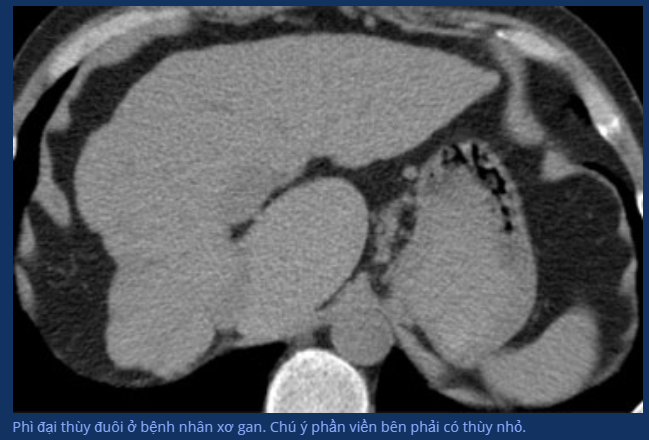

- Thùy đuôi: một thế giới khác biệt. Có thể được cấp máu bởi tm cửa trái hoặc phải, đổ máu trực tiếp về tm chủ dưới không liên quan gì tm gan